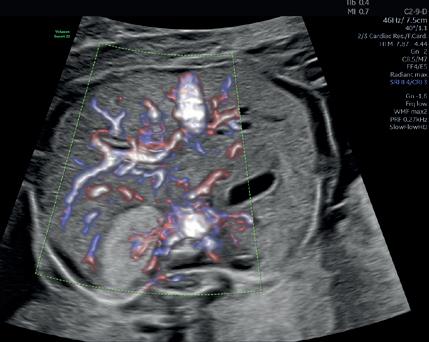

τμήματος Fetal Medicine, υπό την εποπτεία του καθηγητή Κύπρου Νικολαϊδη στο King’s College Hospital. Από το 2000 και για δύο χρόνια, προσέφερε τις υπηρεσίες της στο Αρεταίειο Νοσοκομείο Αθηνών, καθώς συμμετείχε στις δραστηριότητες του Τμήματος Υπερήχων και Εμβρυομητρικής Ιατρικής και στις δραστηριότητες της Β’ Μαιευτικής-Γυναικολογικής Κλινικής Πανεπιστημίου Αθηνών. Στο ίδιο νοσοκομείο και για τα έτη 2003-2006 εργάστηκε ως Επιστημονικός Συνεργάτης στο Τμήμα Υπερήχων και Εμβρυομητρικής Ιατρικής της Β’ Μαιευτικής και Γυναικολογικής Κλινικής του Πανεπιστημίου Αθηνών. Από το 2023 είναι Clinical Instructor του Nicosia University.